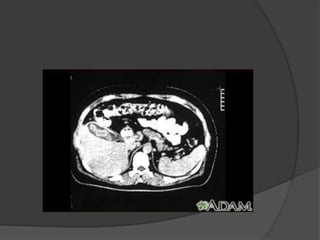

 Tomografía computarizada

 Ecografía abdominal Tomografía computarizada  Radiografía abdominal